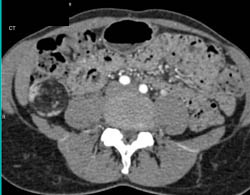

Patent Stent in the Right Renal Artery